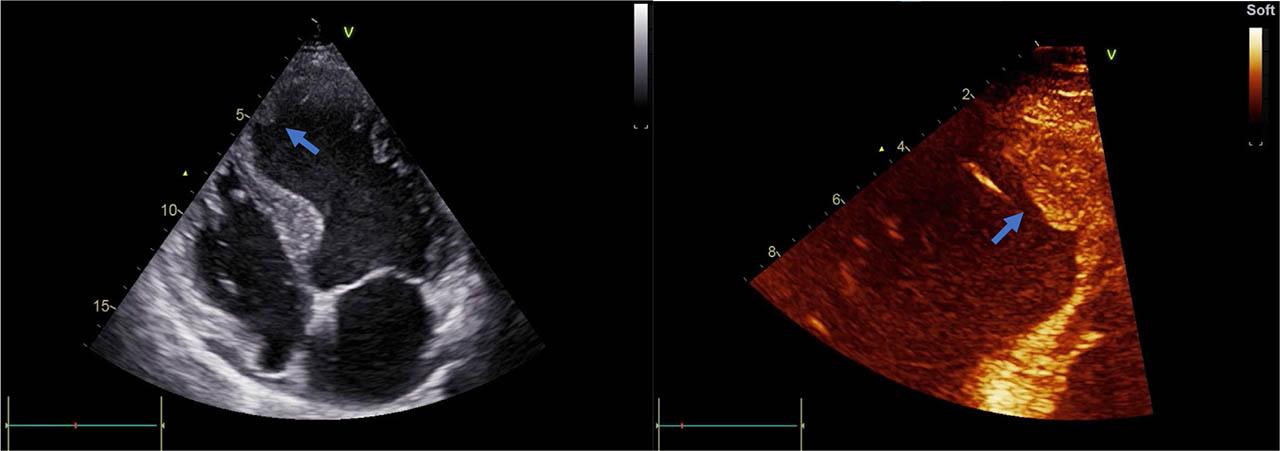

Transthoracic echocardiography (TTE) is the technique most often used for LVT diagnosis, as it is widely used to rule out post-MI mechanical complications and evaluate post-infarction LV structure and function. LV thrombus on echocardiography is defined as an echo-dense mass separate from the endocardium with well-defined edges, frequently adjoining a hypokinetic, akinetic or aneurysmal myocardium that is seen from at least two views [7]. The diagnostic efficiency is influenced by image quality, in order to exclude artefacts and rule out trabeculae and false tendons [3]. To decrease the potential of false-positive diagnoses of thrombus, field-depth and gain settings should be additionally adjusted, together with the use of different carrier frequencies and with transducers in various orientations and positions [5]. Figure 2 exemplifies the echocardiographic aspect of apical septal wall left ventricle thrombus.

Figure 2

Transthoracic echocardiography of the left ventricle. Thrombus (arrows) attached to the apical septal wall in a patient with ischemic cardiomyopathy.